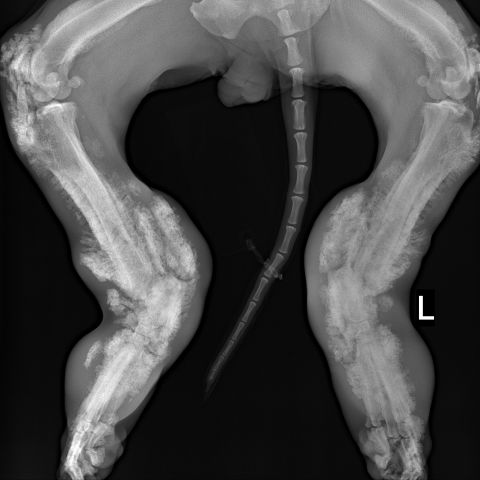

Species: Dog

Specimen: Radiograph

Shown: Hypertrophic osteopathy (Marie's disease) in pulmonary neoplasia